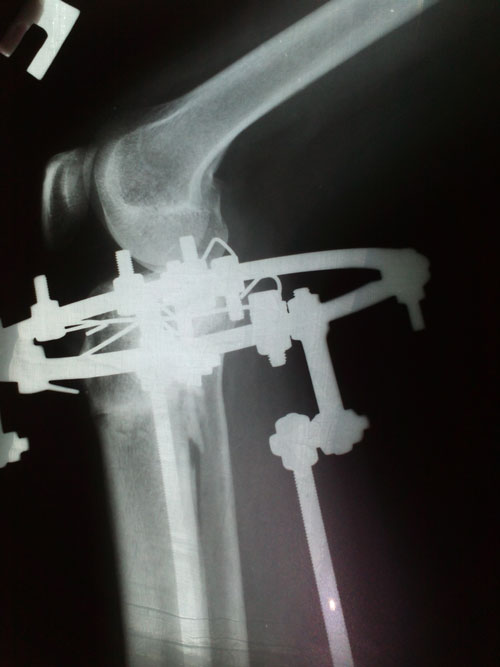

- Хирург: Онипко Н.Н.

- Диагноз: о-образная деформация нижних конечностей

- Дата операции.: 12.03.2013

38 дней с момента операции.

Ножки в норме, продолжаем фиксацию!

Дата операции 15.03.2013г.

Дата снятия аппаратов 17.05.2013г.

Срок лечения 62 дня.